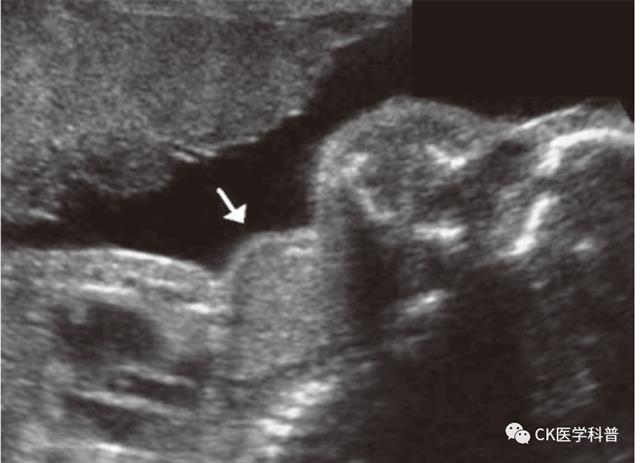

9-1妊娠期对甲状腺结节患者要详细询问病史、完善体格检查、测定血清TSH 和做颈部超声 A

b如果TSH 水平正?;蛏?,应根据结节的声像学特征决定是否做FNA A

9-2妊娠期间可以做FNA。如果甲状腺结节良性可能性大,FNA 可以推迟至产后进行。如果甲状腺结节细胞学检查为良性,妊娠期不需要特殊的监测 A

9-3妊娠早期发现的乳头状甲状腺癌应该进行超声监测,每3 个月复查甲状腺超声,监测肿瘤的增长速度。如果妊娠中期结节仍然保持稳定,或者是在妊娠后半期发现的结节,手术或许可以推迟到产后 C

9-4妊娠早期发现暂不手术的DTC,每3 个月复查甲状腺超声,监测肿瘤的增长速度。给予LT4 治疗,治疗目标是控制血清TSH 在0.3~2.0 mU/L C

9-5如果DTC 在妊娠24~26 周前持续增大,或者发生淋巴结转移,推荐手术治疗 B

9-6DTC 的手术时机应当选择在妊娠中期的后期,此时手术母亲和胎儿风险减小 B